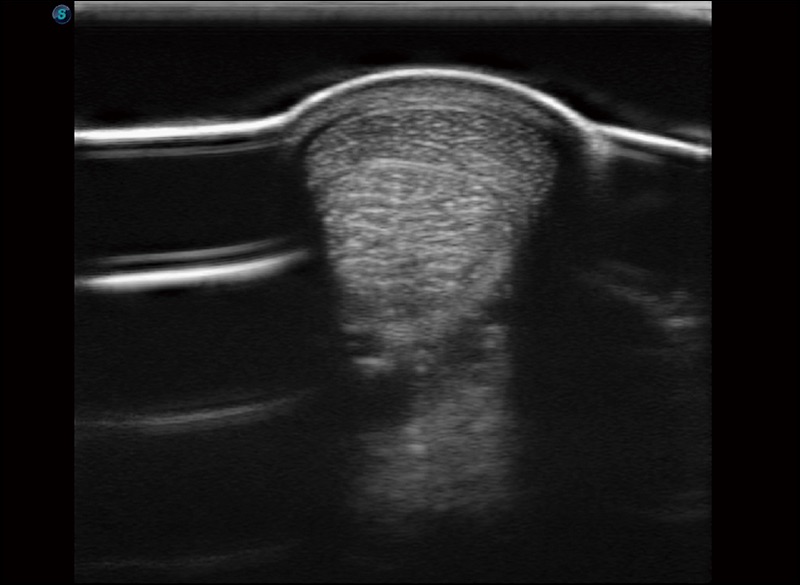

实时宽景成像

可实时观察感兴趣区域和病变位置